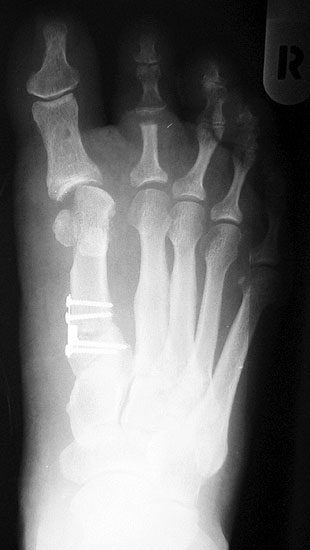

Die dorsoplantaren Röntgenaufnahmen zeigen eine Open-wedge Technik mit der normalerweise ein erhöhter intermetatarsaler Winkel gut zu korrigieren ist (Abbildung 3). Die Wirksamkeit einer Basisosteotomie ist umso größer, je proximaler diese durchgeführt wird. Je weiter distal die Osteotomie, umso geringer die Korrektur. Auf den postoperativen Bildern ist der distal unverändert große Abstand zwischen Metatarsale I und Metatarsale II erkennbar, bei gleichzeitiger Subluxation des Großzehengrundgelenks und dezentrierten Sesambeinen. Darüber hinaus finden sich initiale degenerative Veränderungen im Großzehengrundgelenk. Klinisch bestand eine hohe Weichteilspannung, bei verkürzter Extensor- und Flexor hallucis longus Sehne.  Daher wurde ein verkürzendes Verfahren zur Revision gewählt (Abbildung 4). Die Lapidusarthrodese stellt ein sehr zuverlässiges Verfahren zur Behandlung von Hallux valgus Rezidiven dar 9. Die Fusion des Tarsometatarsale-I-Gelenks kombiniert Stabilität mit einem hohen Korrekturpotenzial. Aufgrund der verfahrensimmanenten Verkürzung des ersten Strahls und der in diesem Fall bereits präoperativ vorhandenen Transfermetatarsalgie wurde die Entscheidung für eine verkürzte Weil-Osteotomie am zweiten bis fünften Strahl gefällt. Die Kombination beider Verfahren führte zu einem homogenen Metatarsale-Index und zu einer gleichmäßigen plantaren Druckverteilung 10. Die Hallux valgus interphalangeus Fehlstellung wurde mit einer Akin-Osteotomie korrigiert.